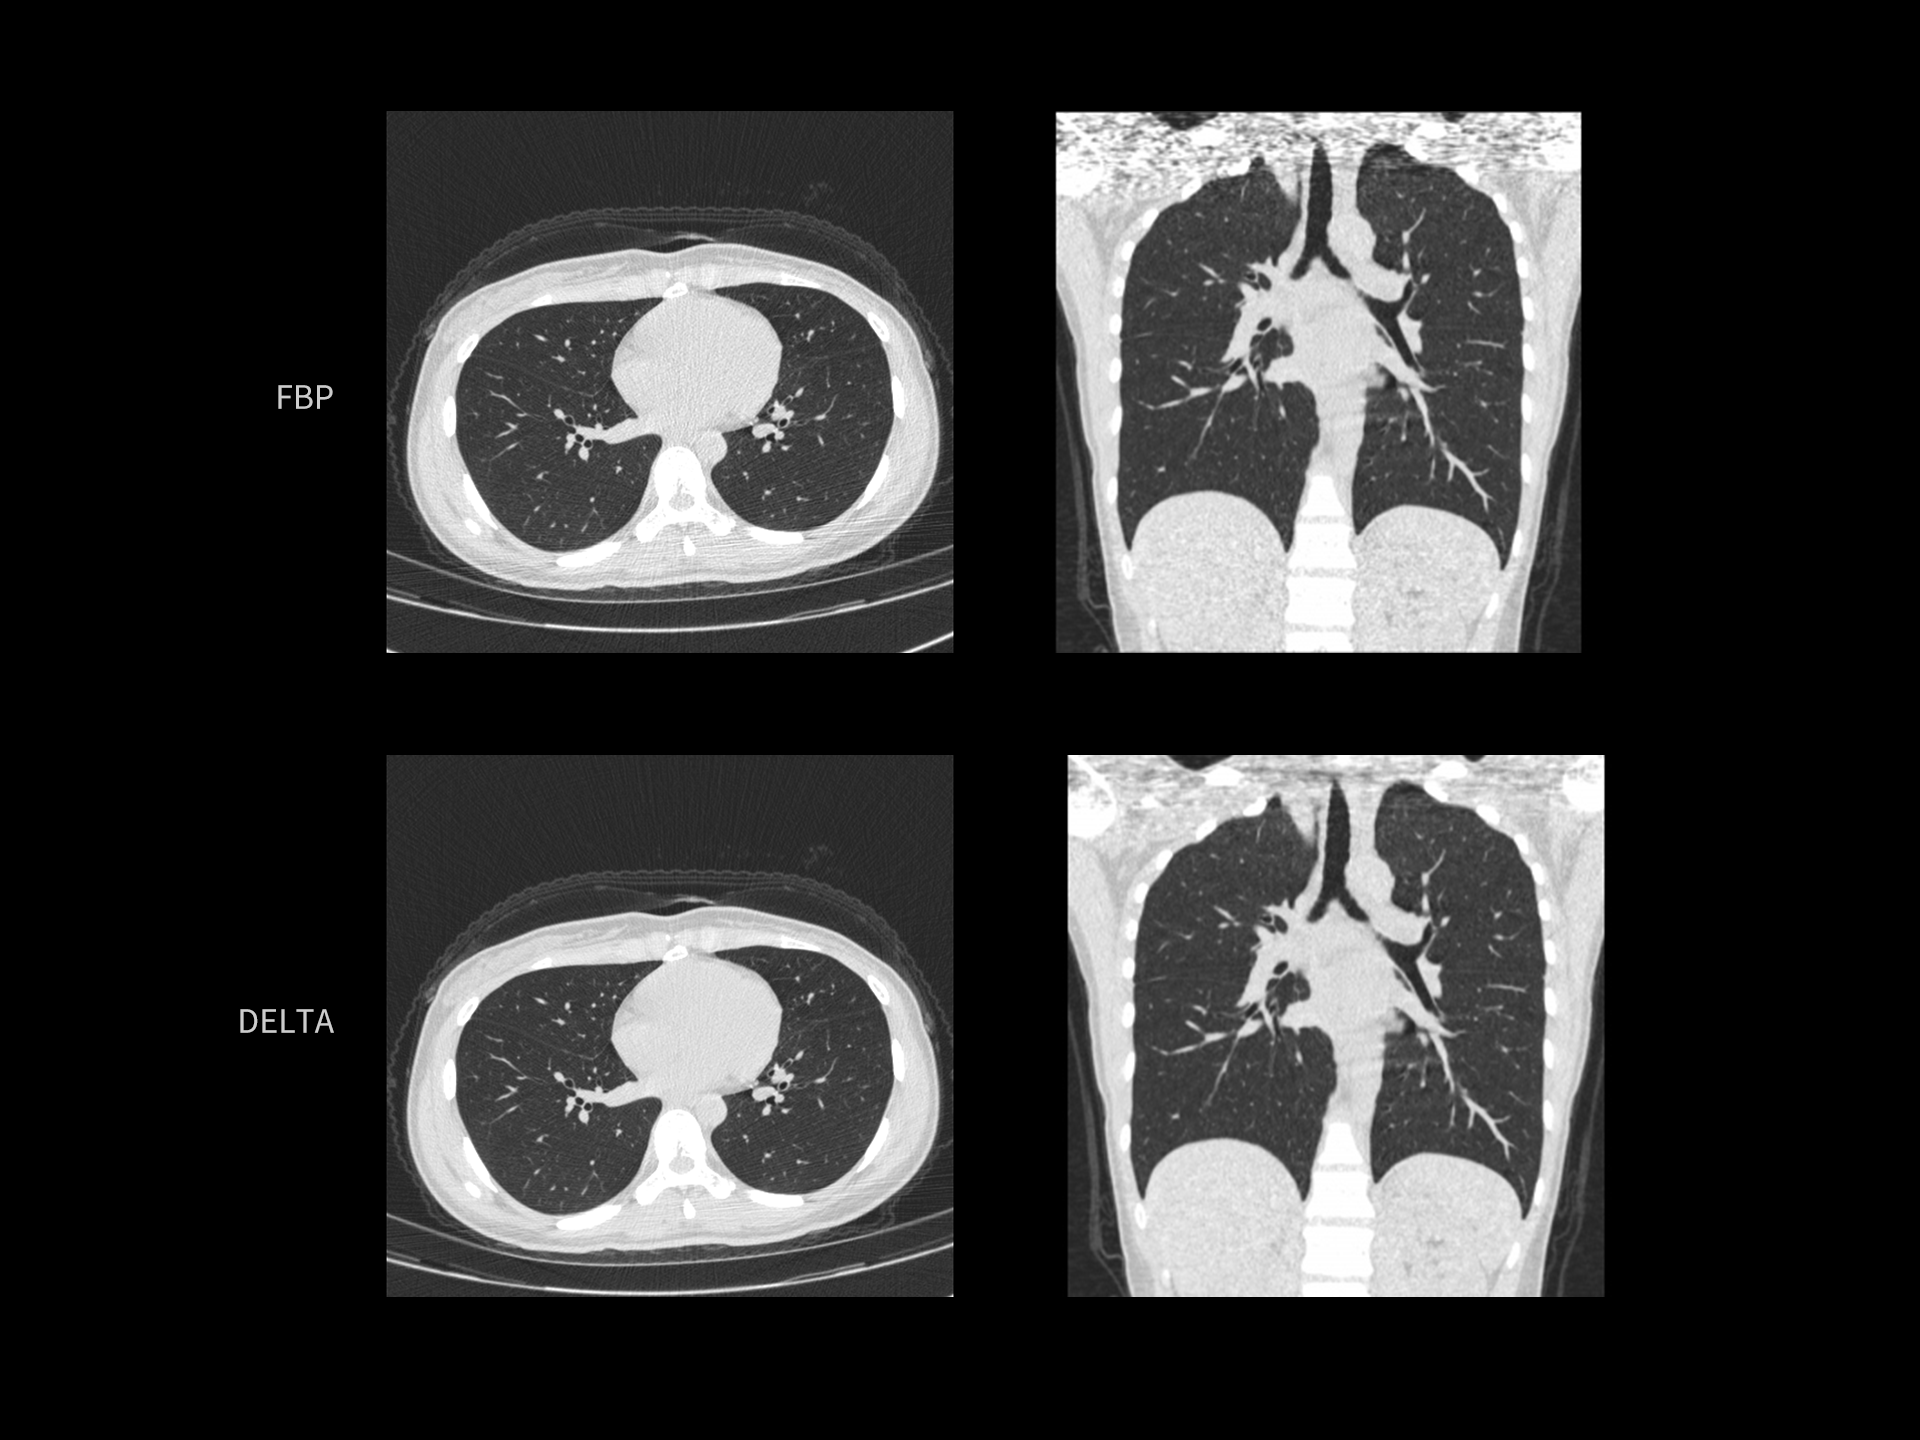

DELTA ridică standardul calității imaginii în toate dimensiunile

Spre deosebire de metodele convenționale precum Filtered Back-Projection (FBP) și Model-Based Iterative Reconstruction (MBIR), tehnologia DELTA oferă un echilibru optim între calitatea imaginii, doză redusă de radiații și viteză mare de reconstrucție.

Prin această performanță, DELTA stabilește un nou standard în imagistica CT.

DELTA îmbunătățește vizualizarea texturii pulmonare în scanările cu doză redusă

| Parametri scanare |

kV: 60 mAs: 210 CTDIvol: 1.8 mGy Doză efectivă: 0.8 mSv |

| Parametri reconstrucție |

Matrice: 512 × 512 Grosime secțiune: 1.0 × 0.5 mm HIR: B_SHARP Nivel DL-Denoise: 3 WW/WL: 1500 / -500 |

| Contrast | — |